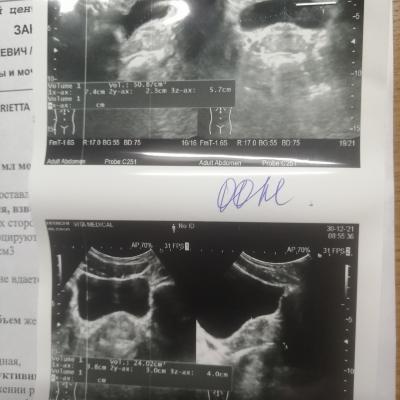

Здравствуйте, появились боли при мочеиспускании и боли в заднем проходе, в промежности. Я сходил на узи, объем простаты 24 см 3, толщина целых 4 см. Это же не норма в моём возрасте, мне всего 27 лет. Но в заключении узи норма во всем, ни воспаления, ни чего то ещё. Но в заднем проходе сильно болит и сжет. Был у практолога, он сказал что нет патологии по его части. Скажите, что с размерами простаты, они же сильно увеличены и отклоняются от нормы?